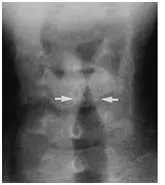

2歲男童半夜因發燒及呼吸窘迫被帶⾄急診求診,問診有 Hoarseness 和Barking cough 的症狀,聽診有Stridor ,X光檢查如附圖,下列敘述何者錯誤?

A⽩⾊箭頭標⽰稱為尖塔徵象( Steeple sign )

X 光片為頸部正面(AP)投影,影像中央可見氣管輪廓。兩個白色箭頭指向聲門下(subglottic)區域,該處氣管兩側管壁對稱性向內收窄,形如教堂尖塔的輪廓,即所謂的「尖塔徵象(steeple sign)」。正常氣管兩側管壁在聲門下應呈平行或略外擴的形態;此影像中聲門下管腔明顯變窄,是聲門下黏膜水腫的典型X光表現,高度提示哮吼(croup)的診斷。需注意,steeple sign 僅在約 50% 的 croup 病例中出現,臨床診斷仍以病史與症狀為主。

(A) ✅ 正確陳述 — 白色箭頭所指為「尖塔徵象(steeple sign)」,這是 croup 在頸部 AP X 光中聲門下對稱性狹窄所形成的教堂尖塔狀輪廓,描述正確。

(B) ✅ 正確陳述 — 2 歲男童半夜出現發燒、Hoarseness(聲音嘶啞)、Barking cough(犬吠樣咳嗽)、吸氣性 Stridor,加上 X 光有 steeple sign,最可能診斷為哮吼(croup),描述正確。